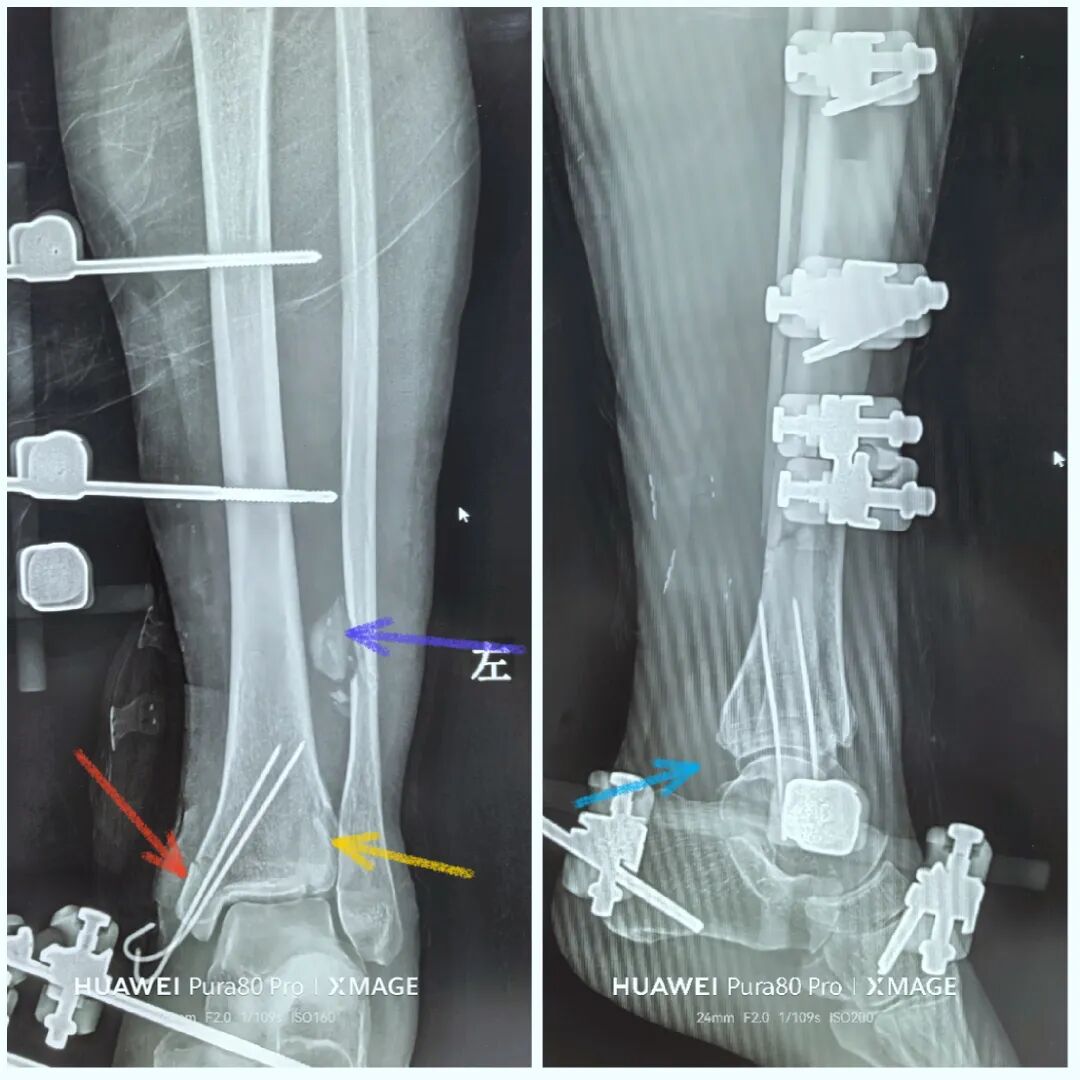

术后复查:

下胫腓关节复位良好

但前侧Chaput骨块

后侧volkmann骨块都移位